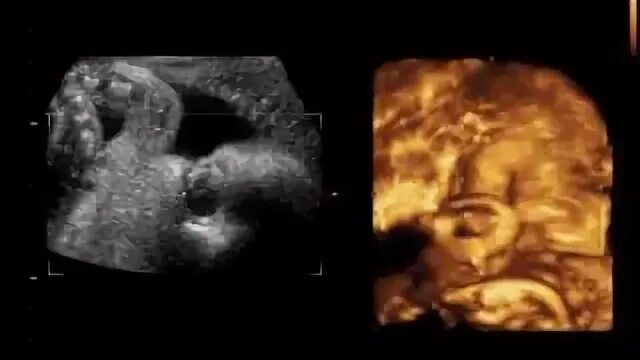

16 неделя можно ли узнать пол ребенка